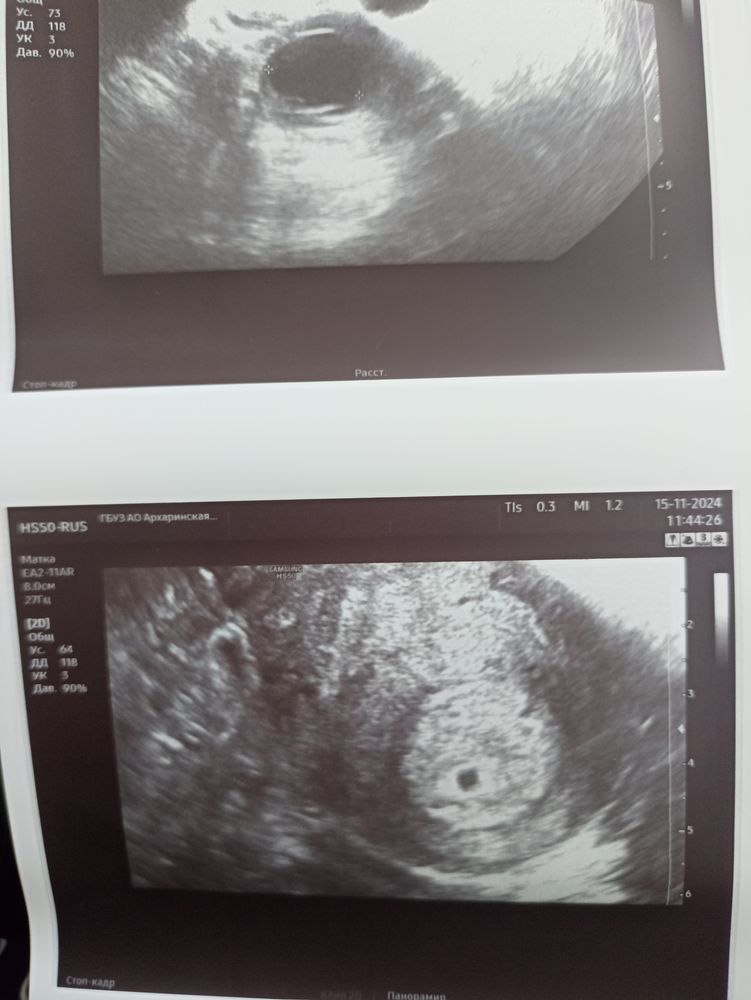

Прощай моя бусинка😭 все таки мое кровотечение закончилось выкидышем... Все вышло само, по узи все чисто. Радует только то что само все вышло и ненадо чиститься. Теперь новые планы и новая надежда🙏